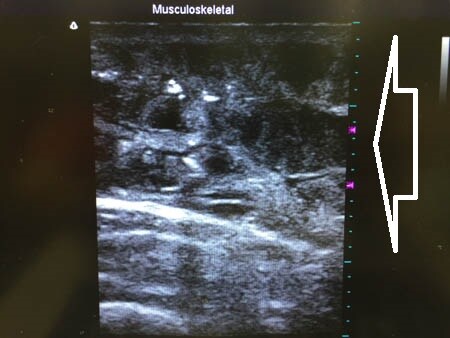

左二の腕

↓ ↓ ↓

上の画像の部分の皮下脂肪層をつまんでみましょう。